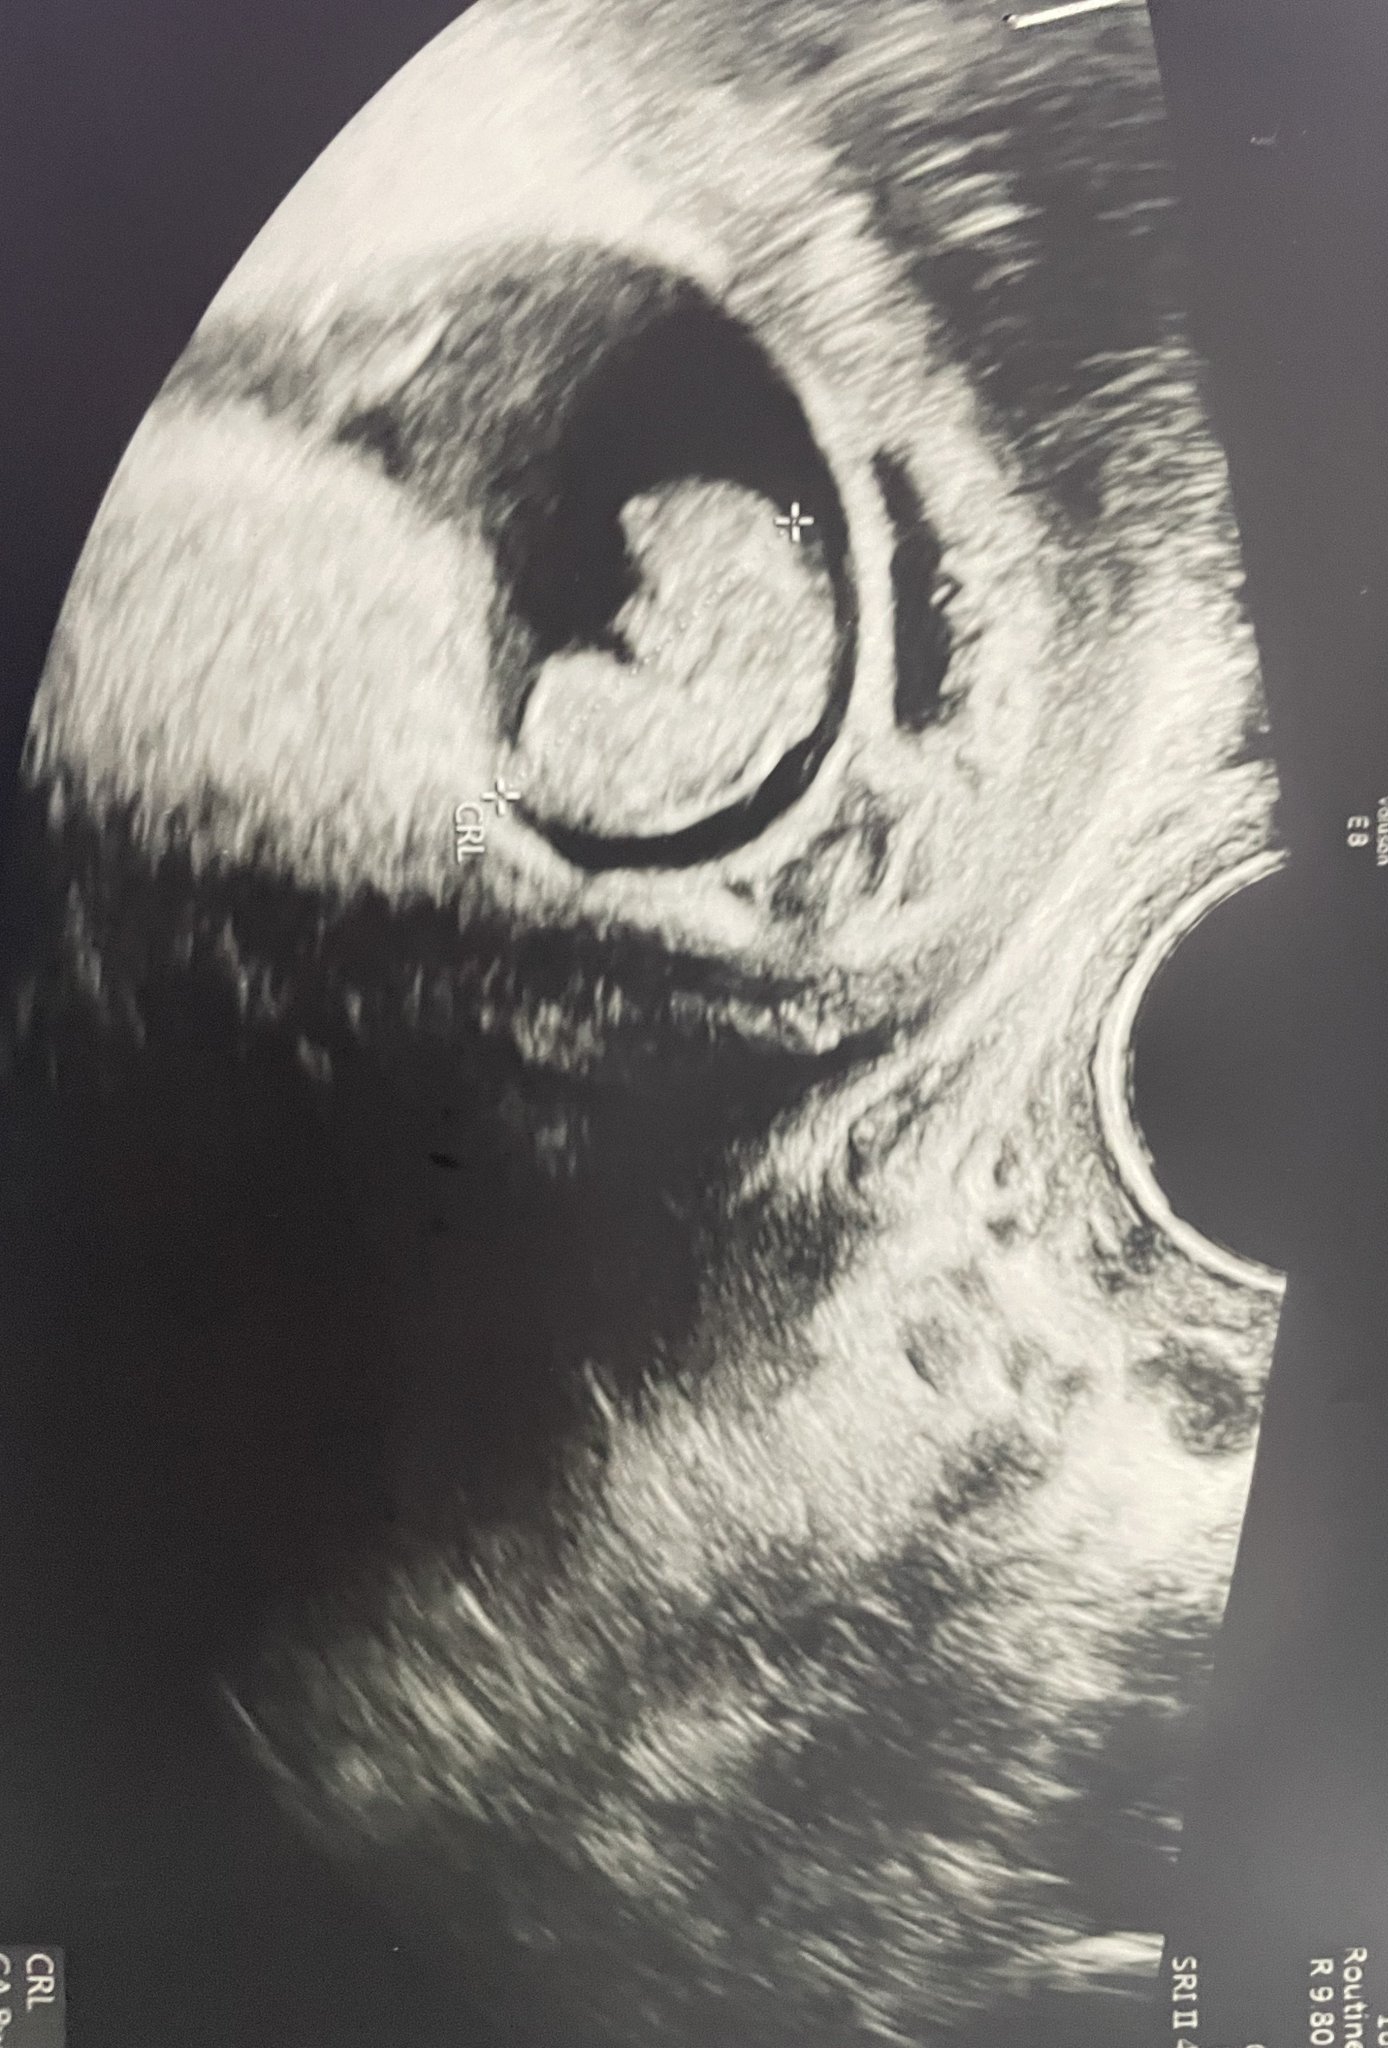

Здравейте значи бях на лекар миналата седмица и каза че в кухо яйце  предписа ме лекарства за аборт прокървях 1 ден след това беле кафяво и събота и неделя нямах никакво кървене та отидох аз да видя изчистена ли съм то па в понеделник  се установи че има ембрион с пулс прикачвам тази снимка тук доктора каза че в кухо яйце според вас кухо яйце ли е ?

И тази преди 2 дни когато бях на лекар